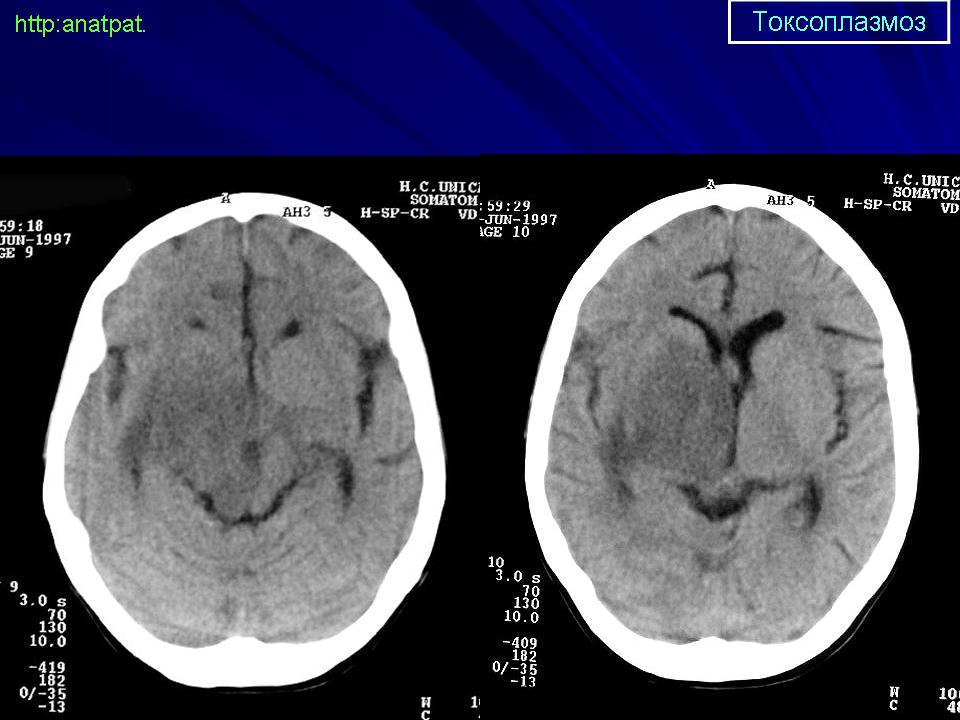

Пато морфологи я. Патоморфологические изменения при приобретенном токсоплазмозе изучены в экспериментах на животных. Установлено, что в центральной нервной системе развиваются явления некротического перивентрикулита, мелкие очаги некроза в субкортикальном белом веществе. В сосудах головного мозга, мягкой мозговой оболочки и хориоидальных сплетениях отмечаются признаки серозно-пролиферативного воспаления. Обнаруживаются также глазные патологоанатомические изменения (типа ретинита, хориоидита, иридоциклита) и изменения во внутренних органах (сердце, легкие, печень, селезенка).

Врожденный токсоплазмоз чаще, чем приобретенный, приводит к летальному исходу. В головном мозге умерших обнаруживаются более или менее значительные очаги обызвествления, участки размягчения мозгового вещества, полости, заполненные жидкостью. Как правило, отмечается гидроцефалия, обусловленная воспалительной и рубцовой облитерацией водопровода среднего мозга, отверстий Люшка или других участков ликворных путей. Истон-чение вещества полушарий мозга может достигать степени их полного исчезновения.

Особенно характерна триада симптомов: хореоретинит, гидроцефалия, очаги обызвествления в головном мозге. Кроме того, отмечаются менингеальные знаки, тонические и клонические судороги, парезы, параличи, олигофрения.

Неврологические симптомы могут сочетаться с пневмонией, миокардитом, гепатоспленомегалией, с выраженной желтухой. В спинномозговой жидкости отмечается лимфоцитарный плеоцитоз (до 500 • 106 в 1 л), ксантохромия (“канареечный” ликвор). На рентгенограмме черепа обнаруживаются обызвествления в глубинных отделах головного мозга, сосудистых сплетениях. Как и приобретенный, врожденный токсоплазмоз может протекать остро, подостро и хронически.

Церебральный токсоплазмоз.

Церебральный токсоплазмоз